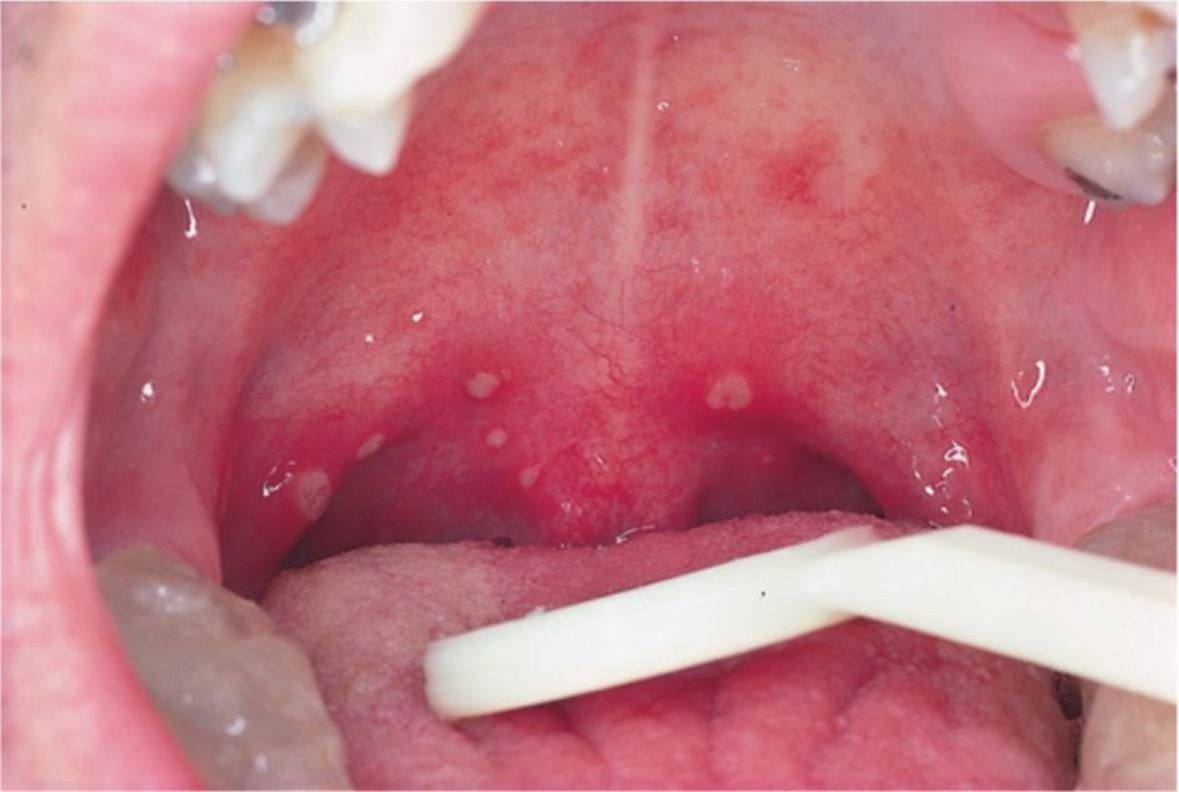

En este marco, explicaron que "un enantema es un sarpullido en las membranas mucosas". "Es muy común en los pacientes con enfermedades virales, como la varicela y la enfermedad de las manos, los pies y la boca. Una característica de muchos sarpullidos virales es que afectan a las membranas mucosas", detallaron.

"Se trata de un signo de la mucosa oral. En realidad, el coronavirus produce lesiones cutáneas y este signo podría estar relacionado con un exantema de la piel. Al mismo tiempo, podría estar vinculado al dolor de garganta que produce el coronavirus. El enantema, que no produce molestias, es común en patologías virales. Lo vemos en el sarampión, en la varicela y en otras afecciones de origen viral", se precisó.